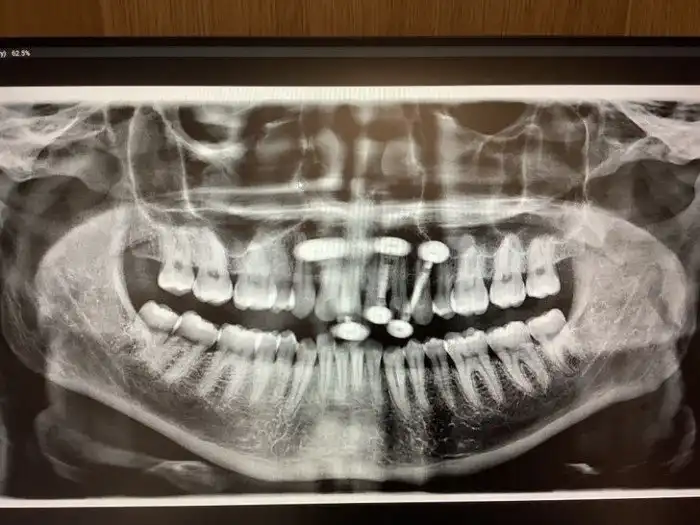

14. "Зубная фея должна мне много денег. Мне 33 года, и вот мои рентгеновские снимки, на которых видны оставшиеся молочные зубы"